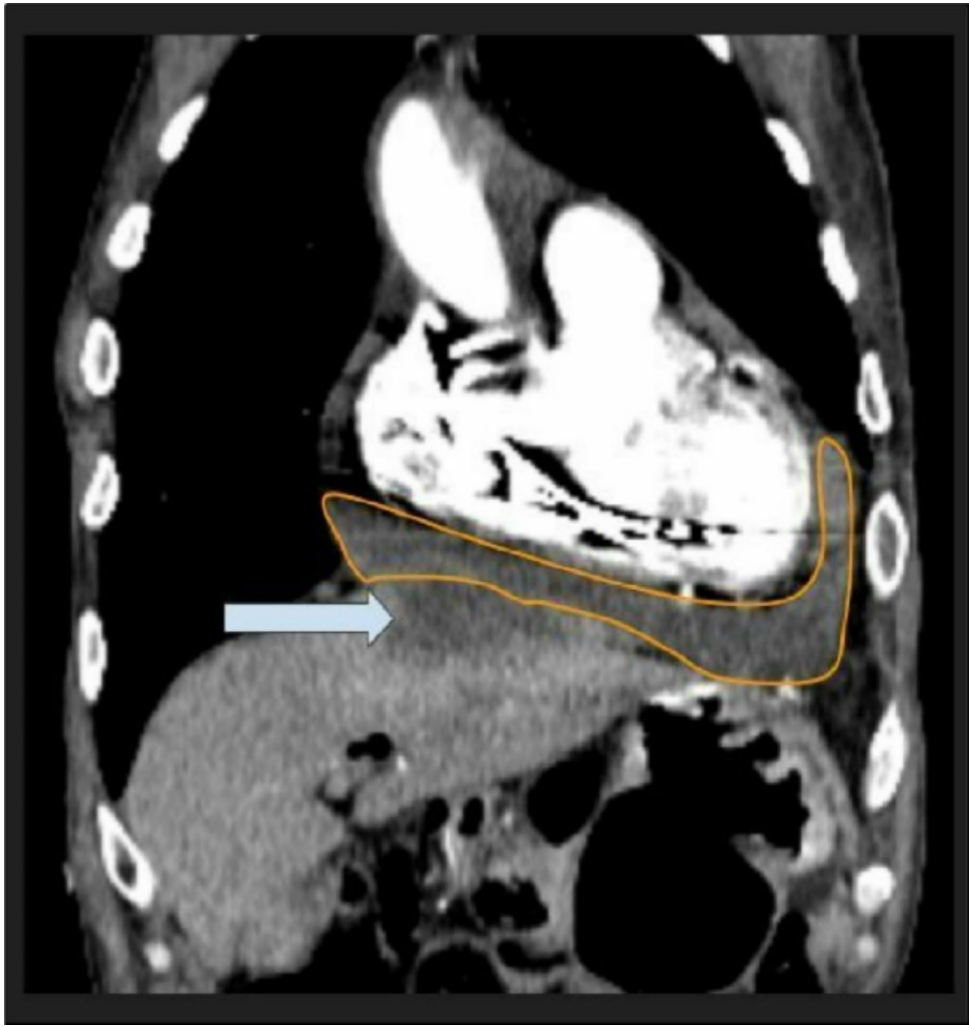

研究团队通过多学科协作,运用床旁超声快速识别心包积液,CT三维重建技术精准定位肝顶部4.8×6.3 cm脓肿与心包的异常交通,创新性采用同步心包穿刺引流(750 ml脓液)和CT引导下肝脓肿引流双管齐下的治疗策略。微生物培养技术锁定Bacteroides fragilis这个"组织破坏专家",其分泌的胶原酶和蛋白酶成为解释瘘管形成的关键分子机制。

76岁男性突发胸痛就诊,兼具胰腺癌术后、心衰(LVEF 20-25%)等复杂背景。特征性的"血压骤降+颈静脉怒张+心音遥远"三联征提示心脏压塞,CT发现肝左叶4.4 cm占位与心包积液的"隔空对话"极具提示性。

研究创新性提出"酶促瘘管形成"假说:Bacteroides fragilis分泌的基质金属蛋白酶(MMP)降解肝被膜与心包间隔胶原,在膈肌薄弱处形成病理性通道。CT显示的"肝顶气泡征"(图3)为此过程提供影像学佐证。